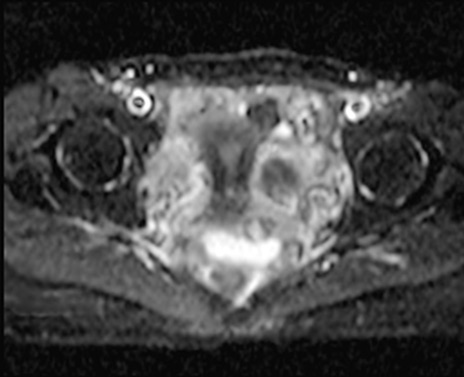

MRI(4日後)